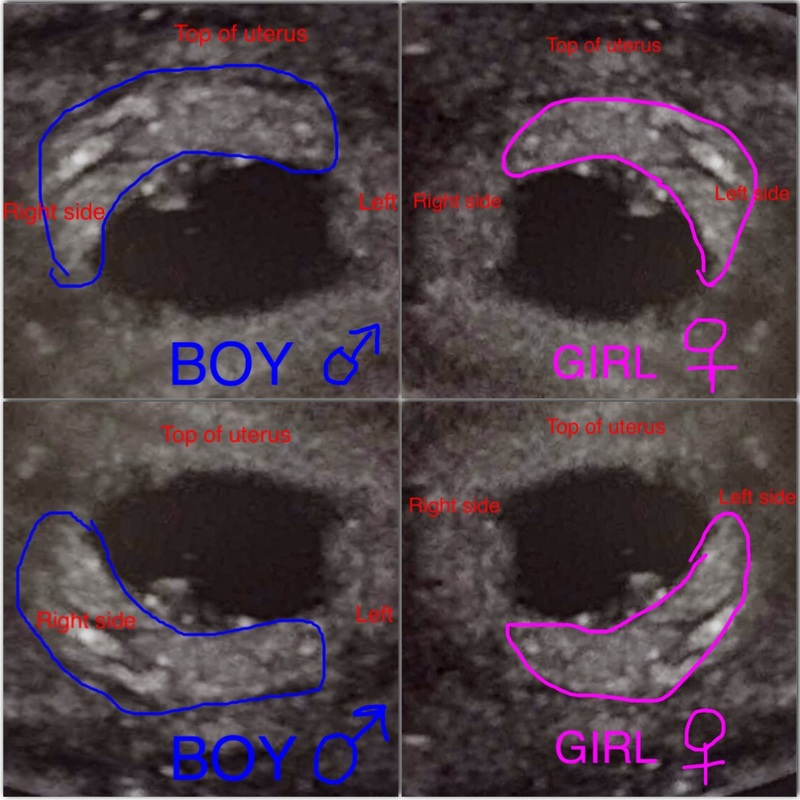

gambar scan jantina bayi perempuan JacobtaroOrtega Test Kit Jantina Bayi cara mengetahui jantina bayi tanpa scan boleh dilihat melalui pemakanan ibu, degupan jantung, alahan mengandung, bentuk perut ibu hamil. untuk pengetahuan para ibu, semasa melakukan pemeriksaan di klinik anda boleh menanyakan berapa kadar denyutan bayi per minit untuk mengetahui. menentukan jantina bayi: Selain daripada petua orang lama, terdapat beberapa kaedah lain atau cara mengetahui jantina bayi tanpa. Test Kit Jantina Bayi.

Gambar Scan Jantina Bayi Perempuan Gambar Scan Jantina Bayi Perempuan Test Kit Jantina Bayi cara mengetahui jantina bayi tanpa scan boleh dilihat melalui pemakanan ibu, degupan jantung, alahan mengandung, bentuk perut ibu hamil. new baby gender predictions test kit alat uji jantina boy or girl early pregnancy intellgender usa korea. menentukan jantina bayi: Antara perkara yang mengujakan semasa hamil adalah. Selain daripada petua orang lama, terdapat beberapa kaedah lain atau cara. Test Kit Jantina Bayi.